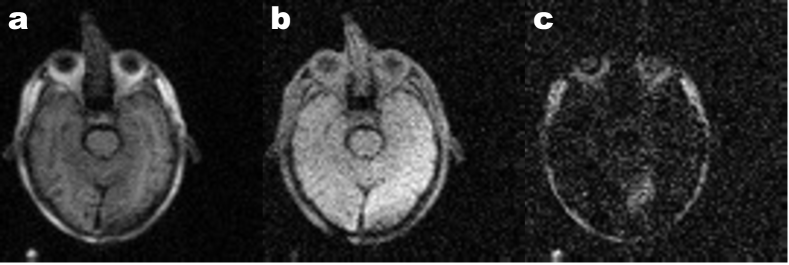

The performance of the proposed method was tested on in vivo FFC imaging patient data. Two data sets obtained from patients scanned for a brain stroke were selected, as part of the PUFFINS study currently taking place at the University of Aberdeen. This study has been approved by the North of Scotland Research Ethics Committee (study number 16/NS/0136) and all the participants agreed for the clinical and FFC imaging data to be used anonymously for research purposes. The scans selected both present a lesion in the ultra-low field regime that could not be easily observed at 200 mT, as illustrated in Figure 2 for patient I. Both cases were assessed from computed tomography (CT) and diffusion-weighted MRI scans as embolic stroke for patient I and multiple embolic events for patient II. FFC measurements were performed using a whole-body FFC scanner [21] using a FFC inversion-recovery spin echo sequence [46] with an echo time of 24 ms, 20 kHz bandwidth, 8.37 MHz acquisition frequency, 10 mm slide thickness and single slice acquisition. The images had a field of view of 290 mm and a resolution of 128 x 128 pixel in-plane with 80 phase encode acquisitions and partial Fourier acquisition (80 lines out of 128). The sample was pre-polarised at 200 mT for 300 ms before each evolution periods with the timings as shown in Table  1, for an acquisition time of 40 min.

Figure 2: FFC images of a stroke patient from the PUFFINS study (patient I). Image obtained at 200 mT evolution field show good signal after inversion (b) and after 455 ms evolution time (a) but low contrast in the lesion, while low-field images at 21 mT (c) show good lesion contrast but most other tissue shows little to no signal.